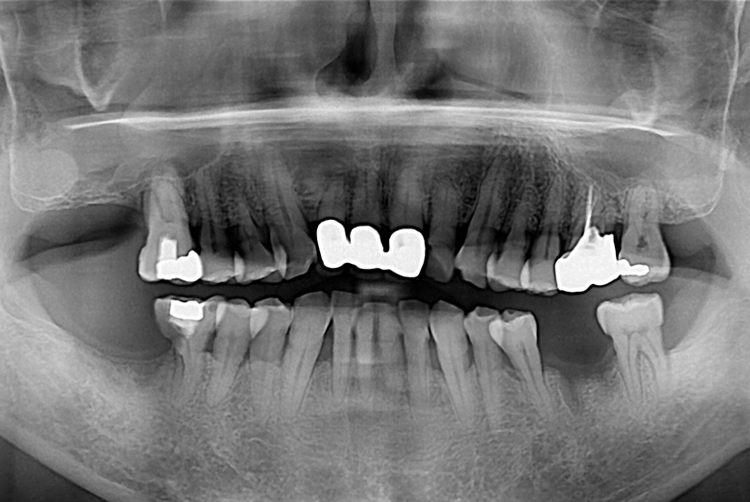

[임플란트] 임플란트

치료전 : 2018-08-17